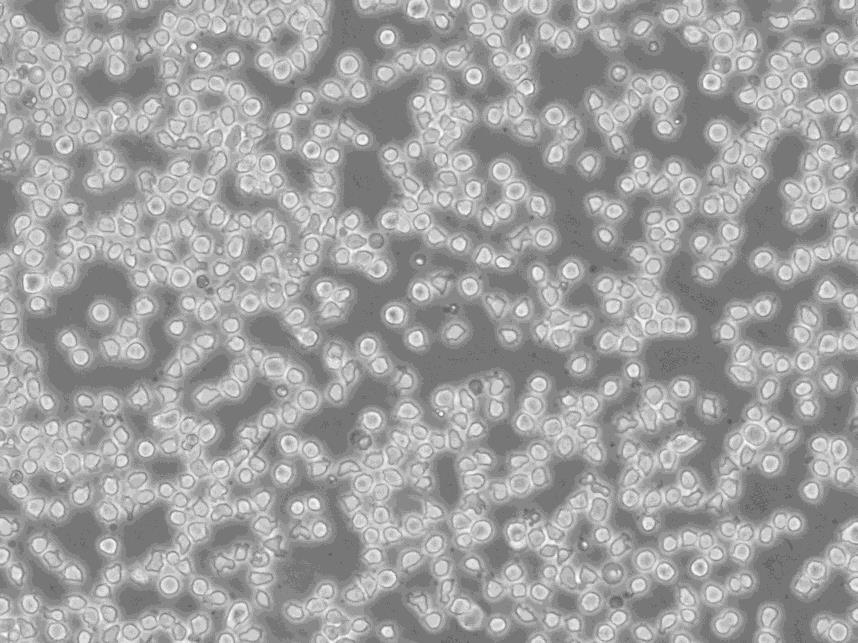

细胞形态:淋巴母细胞样

细胞生长:悬浮

细胞背景资料:弥漫大B淋巴瘤;男性

细胞生长特性:悬浮